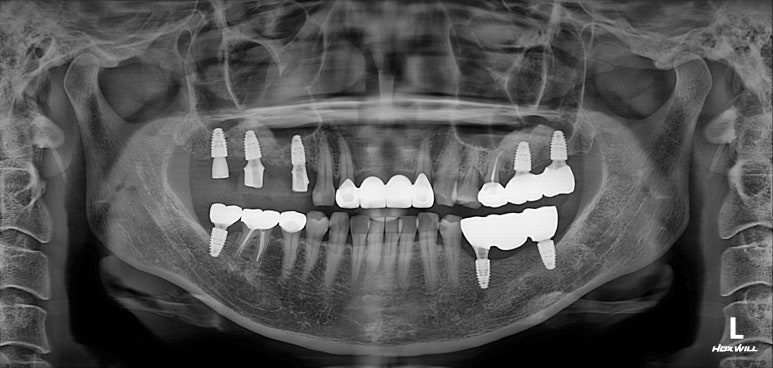

대부분의 수술은 위턱부터 시작합니다.

상악동 뼈이식술을 하면서 임플란트 수술을 시행하였습니다.

왼쪽 위 어금니에 2개, 오른쪽 위 어금니에 3개 총 다섯개의 스트라우만 임플란트를 사용하였습니다.

제 포스팅을 많이 보신 분들은 아실텐데, 상악동 뼈이식술도 함께 진행하였습니다.

내원했을 당시 처음과 비교해보면, 노란선으로 표시된 상악동 뼈이식술 라인을 관찰하실 수 있을겁니다.

상당히 깔끔하게 수술이 이뤄졌네요!

그리고 저희 치과는 치과보존과 전문의 원장님이 함께 계신데, 주황색으로 표시된 두 치아가 깔끔하게 신경치료가 마무리 된 것을 보실 수 있습니다.

깔끔하게 신경치료가 마무리 되면, 보다 조화로운 '교합평면'을 만들어낼 수 있죠.

위턱 임플란트를 심어드리고 3주 뒤에 아래턱 임플란트를 심었습니다.

보통 환자분들이 한 번에 수술을 다 하면 너무 힘들어하시기 때문에, 위와 아래로 수술을 나누어 하게 되는데요.

통상적으로 위턱 뼈가 밀도가 낮아 치유 기간을 한달정도 더 가져가기 때문에 수술은 위턱 수술 먼저 완성 후 아래턱 수술 순서로 진행됩니다.

오른쪽 아래 어금니에 2개, 왼쪽 아래 어금니에 1개 (그리고 사랑니 발치까지) 수술이 잘 이루어졌네요!!

위턱은 상악동 골이식술이 있어 수술시간 1시간 안팎, 아래턱은 30분 안팎 걸렸던 것 같습니다.

그렇게해서 최종완료 후 치과용 파노라마 사진입니다!

치과치료에 대해 잘 모르시는 분이라 할지라도 보고 있으면, 치료가 조화롭게 잘 끝났구나.. 라고 아실 수 있으리라 생각합니다.

제가 제일 좋아하는 치과용 파노라마 비교 사진입니다.

앞으로 나란히를 한 것 같이 평행한 임플란트의 완성도는 항상 카타르시스를 느끼게 합니다.